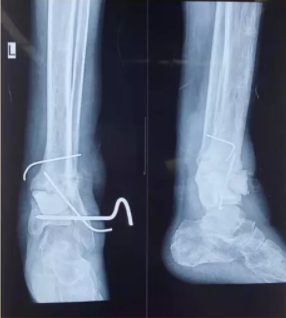

遇到内踝骨折短缩通常需要抗滑或支撑固定,利用U型针可以起到支撑固定作用。

23、克氏针连接空心钉固定内踝骨折

通过标准的方法切开复位内踝骨折。然后使用2枚4.0mm空心带螺纹空心拉力螺钉固定横行骨折。然后使用克氏针固定矢状位骨折。从一枚螺钉的螺钉孔中置入克氏针到相应位置,然后将克氏针尾端折弯成60°,修剪长度后通过另外一枚螺钉的螺钉孔置入骨折部位。